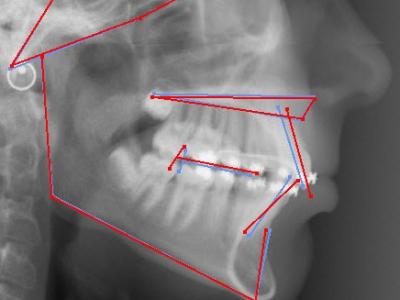

Vues endo-buccales (a, b, c) et téléradiographie de profil initiales avec IMPA=105° (d);

vue endo-buccales (e, f, g) et téléradiographie de profil (h) à 1 an post-opératoire (sans traitement orthodontique) montrant un redressement spontané des incisives mandibulaires avec IMPA=94° et une avancée du point B ;

superposition avec le logiciel Procuste (Rouge = Avant / Bleu = Après) montrant le repositionnement incisif et la croissance mandibulaire (i) ;

vue endo-buccales (j, k, l) et téléradiographie de profil (m) à 4 ans post-opératoires, avec traitement orthodontique multi-attaches et 1 an de contention, l’IMPA est resté stable à 94°.